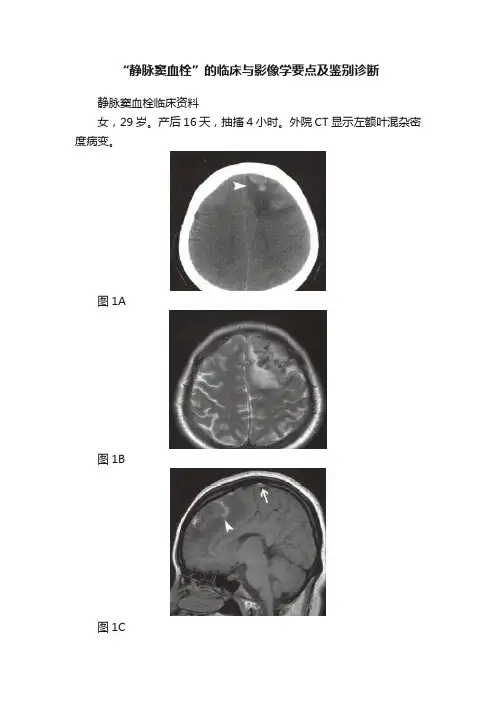

“静脉窦血栓”的临床与影像学要点及鉴别诊断静脉窦血栓临床资料女,29岁。

产后16天,抽搐4小时。

外院CT显示左额叶混杂密度病变。

图1A图1B图1C图1D图2A图2B影像学报告描述轴位CT平扫(图1A),左额叶近似三角形低密度灶,内见斑片状高密度影(无尾箭头),局部脑沟变浅。

轴位T2WI(图1B),左额叶病变呈高信号,内见脑回状及片状低信号。

矢状位T1WI(图1C),左额叶病变为低信号,内见斑片状高信号(无尾箭头),上矢状窦前中部不均匀高信号(箭)。

非增强MRV斜位投影(图1D),上矢状窦前中部信号下降,轮廓不整,内见充盈缺损(箭)。

影像诊断与最后诊断均为:上矢状窦血栓伴左额叶静脉性脑梗死,经DSA造影证实(未列出)及静脉窦溶栓治疗好转后出院。